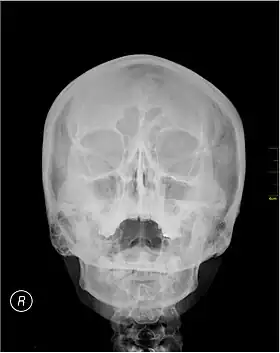

| Waters' view | |

Waters' view (also known as the occipitomental view) is a radiographic view of the skull. It is commonly used to get a better view of the maxillary sinuses. An x-ray beam is angled at 45° to the orbitomeatal line. The rays pass from behind the head and are perpendicular to the radiographic plate. Another variation of the waters places the orbitomeatal line at a 37° angle to the image receptor. It is named after the American radiologist Charles Alexander Waters.

Waters' view can be used to best visualise a number of structures in the skull.

- Maxillary sinuses.

- Frontal sinuses, seen with an oblique view.

- Ethmoidal cells.

- Sphenoid sinus, seen through the open mouth.

- Odontoid process, where if it is just below the mentum, it confirms adequate extension of the head.

Typically, the x-ray beam is angled at 45° to the orbitomeatal line.[3] Another variation of the waters places the orbitomeatal line at a 37° angle to the image receptor,[4] or 30°.[5]